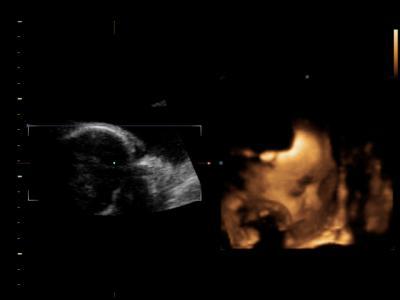

hier unsere tochter inside:-)

meine maus wiegt ca. 1300 g und ist ca. 37,5 cm gross es geht ihr super liegt richitg nur mein arzt sagt ich soll beim gewicht aufpassen hallo hab gerade mal 10 kg zugenommen der ist komisch in der sache^^ hier noch ein foto :-)

Wow, schöne Profilansicht :-) Freut mich dass bei deiner Maus alles in Ordnung ist - ich bin mal gespannt wann sich meine dreht! Die Bemerkung zum Gewicht verstehe ich auch nicht, 10kg ist doch noch im Durchschnitt? LG Katia